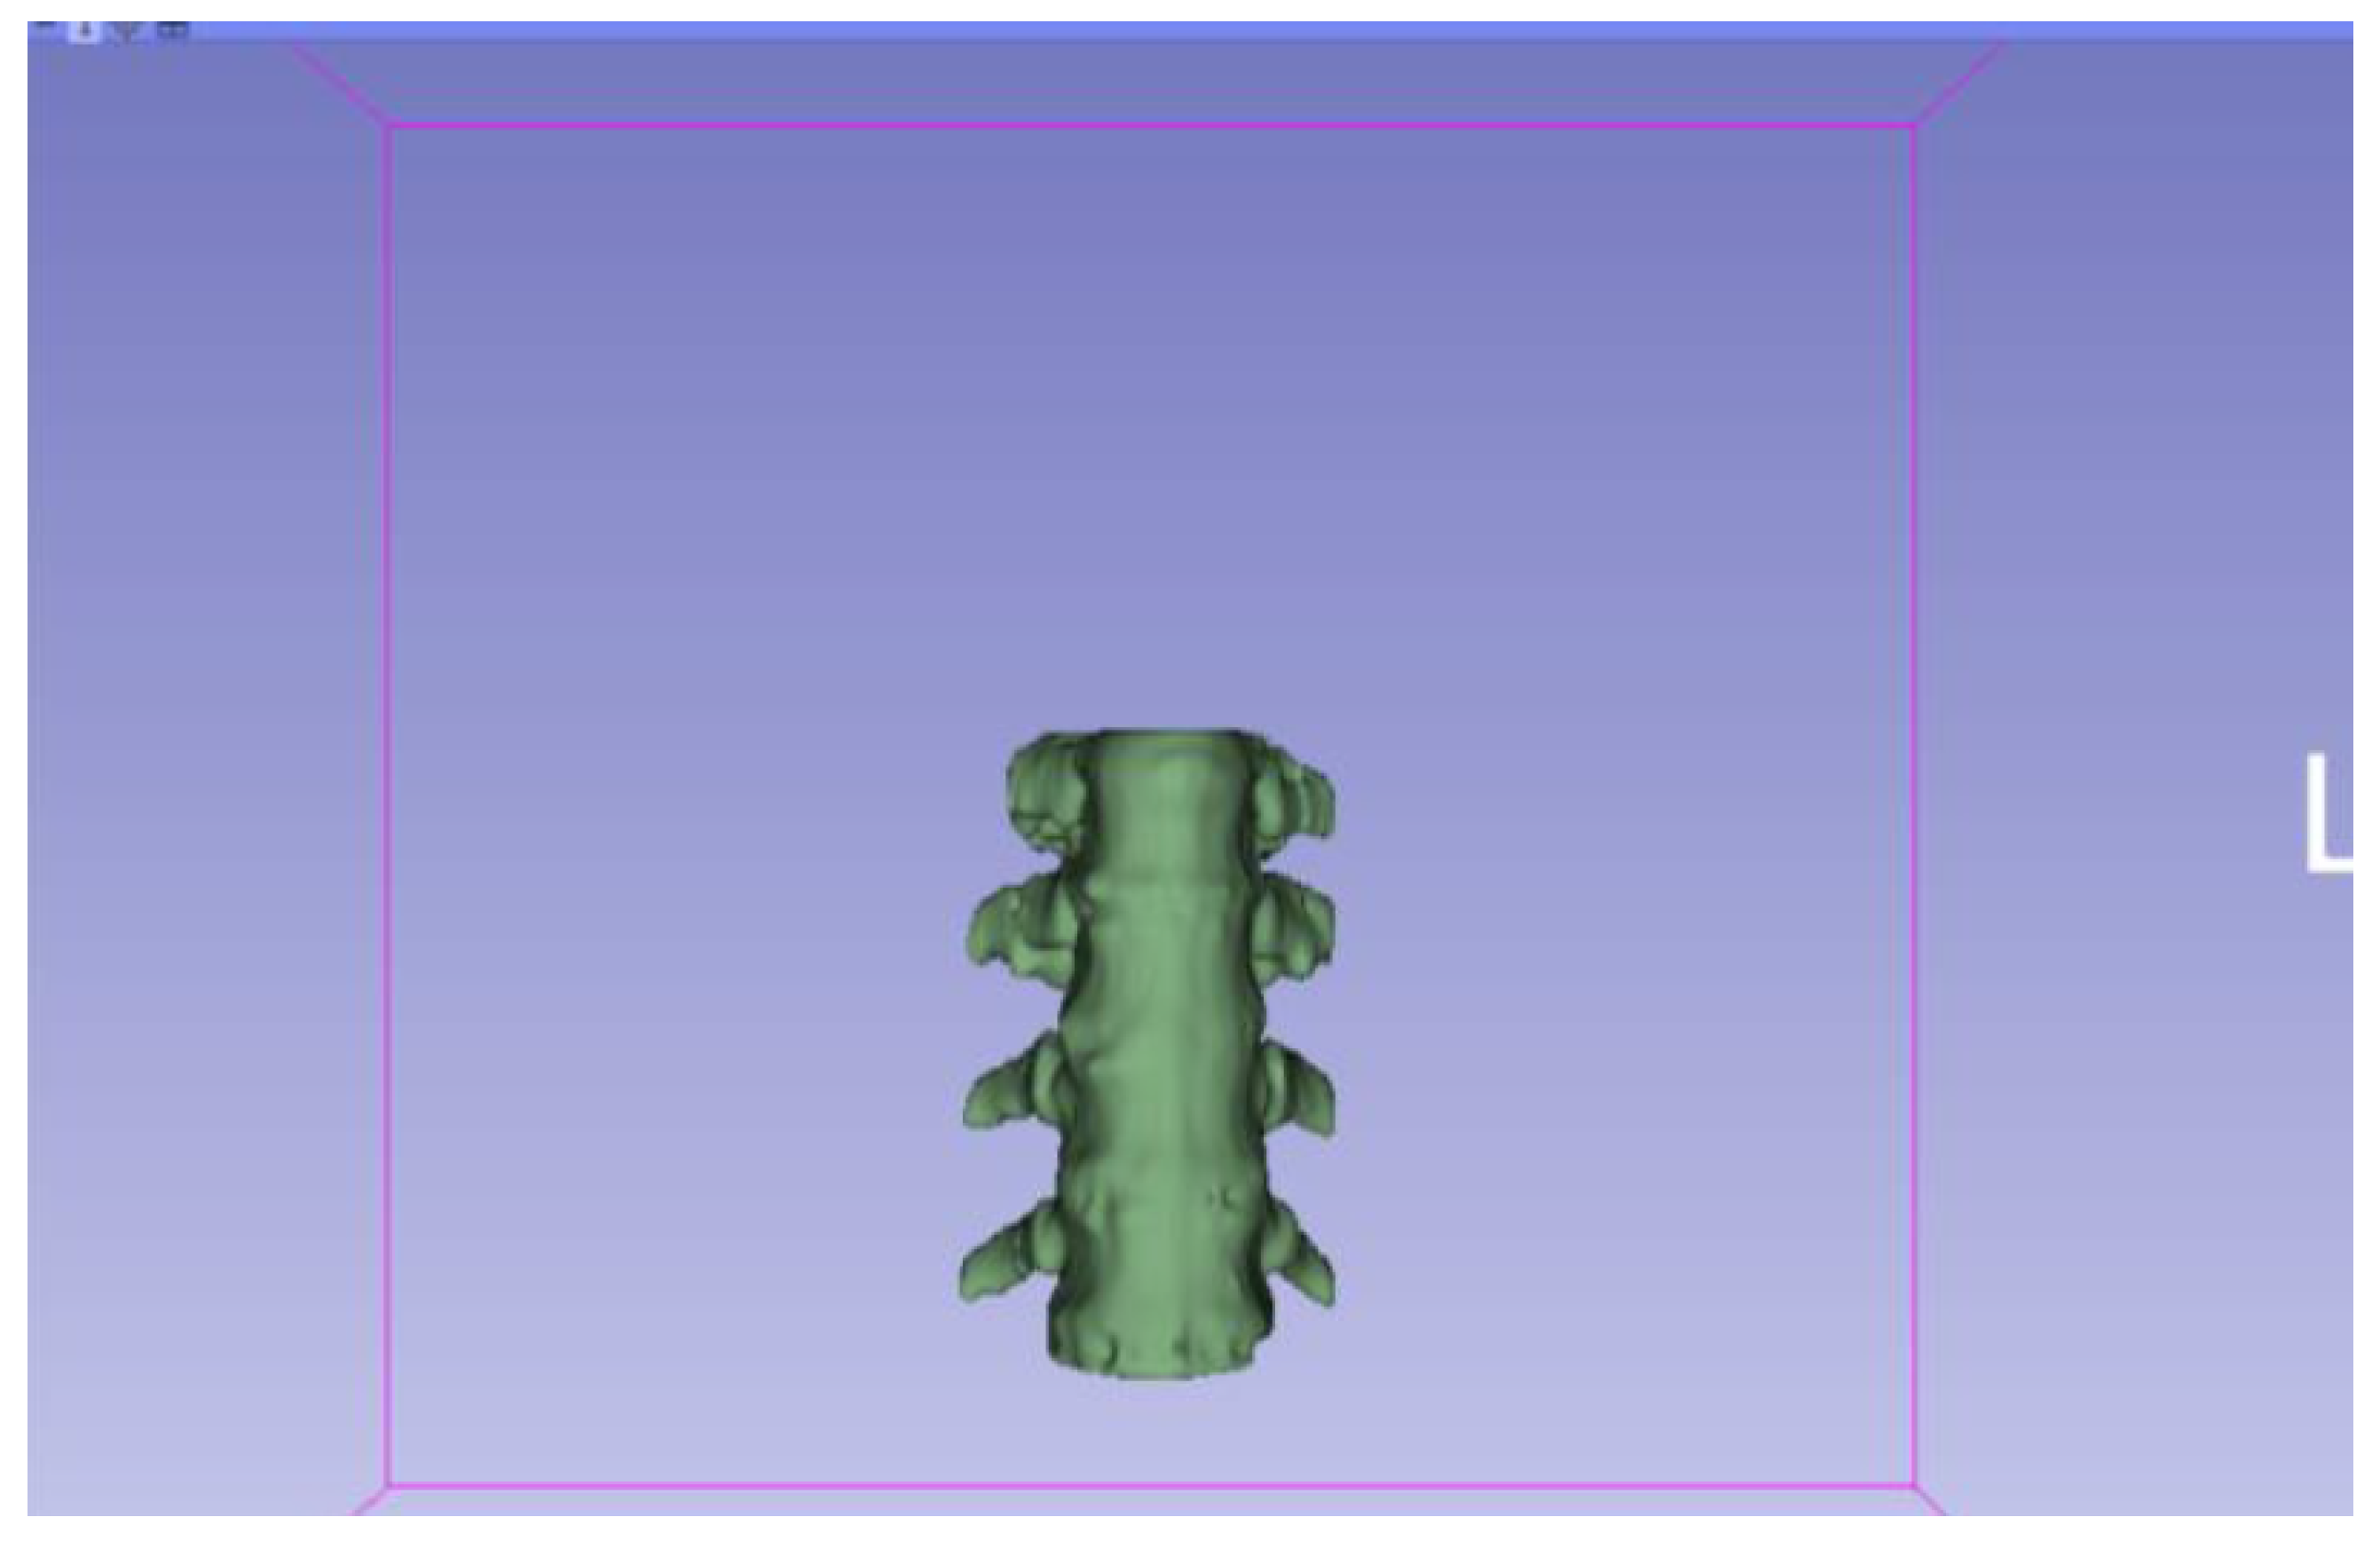

3.1.1. DICOM-to-STL File

| Vertebrae | [150, 300] | Median | 0.8 | 0.18 | 25 |